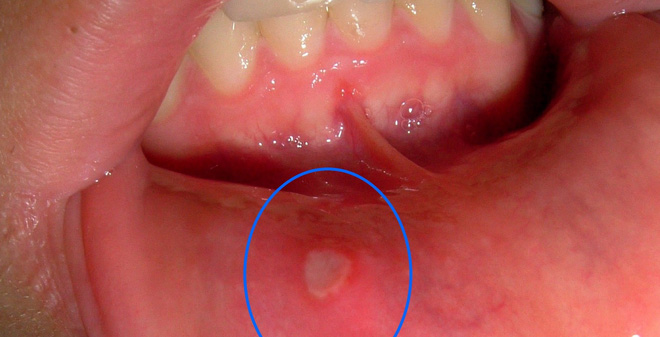

Nhiệt miệng, loét miệng dù chỉ nhỏ xíu cũng sẽ khiến bạn rất đau và khó chịu. Bạn hầu như sẽ không thể ăn ngon trong tình trạng này.

Chúng thường xuất hiện ở môi, lưỡi hoặc bên trong khoang miệng. Đôi khi bạn sẽ phải chịu đựng cơn đau tới hơn 2 tuần liền do vi khuẩn trong miệng làm chậm quá trình lành lại.

Có rất nhiều lý do gây ra các vết loét như bệnh viêm loét miệng, mụn giộp hay thậm chí là ung thư vòm họng hoặc các nguyên nhân đơn giản như suy dinh dưỡng, hệ miễn dịch yếu, vệ sinh kém và dị ứng.

Nếu trong vòng 10 ngày mà vẫn không khỏi bệnh, bạn hãy nhanh chóng đến khám bác sĩ để xem đó có phải là dấu hiệu của vấn đề sức khỏe nghiêm trọng nào không.